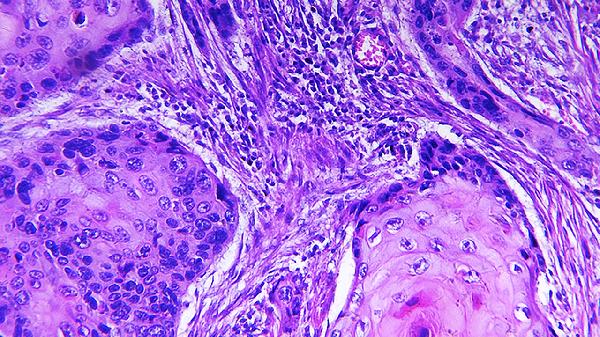

气候变化、汗液浸渍或衣物摩擦等物理因素会加重局部炎症。表现为边界清晰的苔藓样斑块,好发于颈后、肘窝等部位。建议选择纯棉衣物,保持环境温湿度稳定。